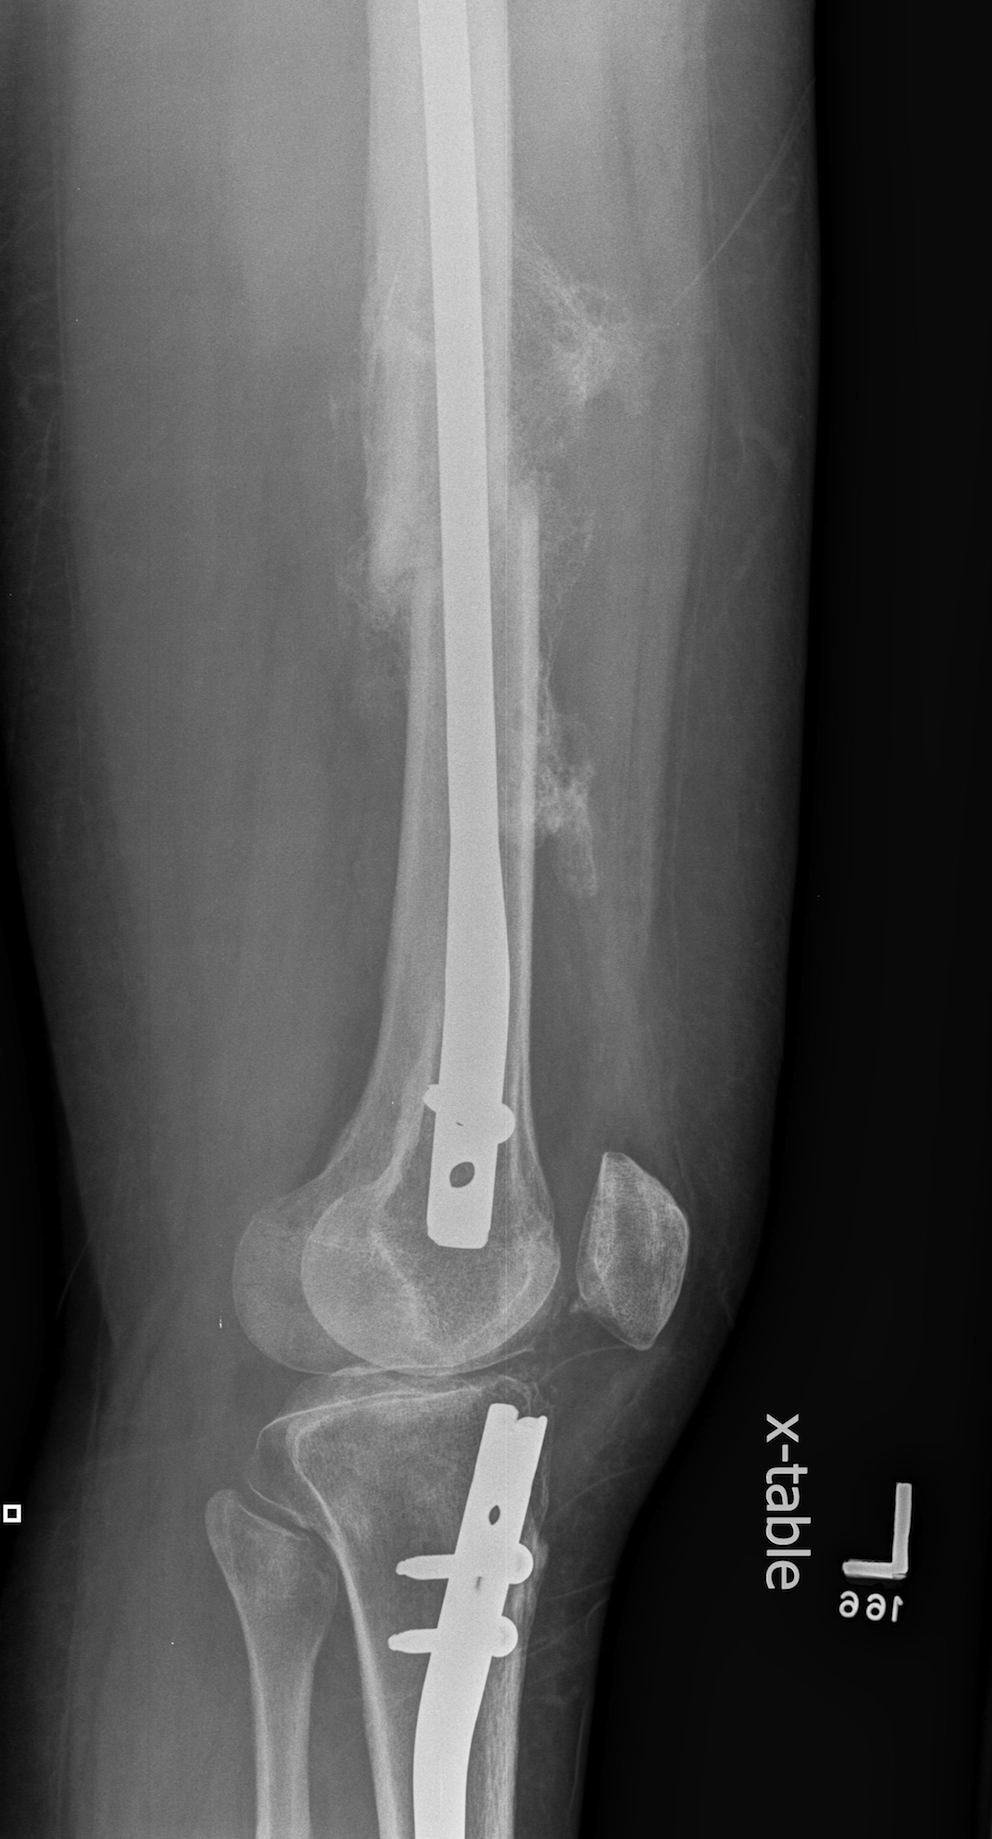

Floating Knee

Ipsilateral femur + tibial fracture

1. Floating Knee

Single incision at knee

- retrograde femoral nail

- tibial IMN if appropriate

High complication rates including non union / malunion, knee stiffness and hetertopic ossification